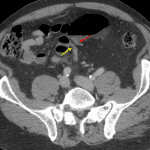

Indication: Generalized abdominal pain

Findings

- Lower chest

- Mild dependent atelectasis

- Abdomen/Pelvis

- Dilated segment of sigmoid colon in the central abdomen with mural thickening, hypoenhancement, and adjacent mesenteric fat stranding

- Abrupt upstream and downstream caliber changes with the afferent and efferent bowel segments adjacent to each other in the left lower quadrant

- No swirling of the sigmoid mesentery

- No pneumatosis, portal venous gas, or pneumoperitoneum

- Small volume free intraperitoneal fluid layering in the anatomic pelvis and tracking into the left inguinal canal without loculated collection

- Fluid density 2.5 cm structure in hepatic segment IVb, compatible with a cyst

- Additional scattered subcentimeter hepatic hypodensities are too small to characterize

- 2 cm structure in the spleen with irregular peripheral enhancement, likely a hemangioma

- Atherosclerotic calcification of the abdominal aorta and branch vessels without aneurysm

- MSK

- No acute findings

- Polyarticular degenerative changes

Diagnosis

- Sigmoid volvulus

Findings concerning for sigmoid volvulus, although there is no swirling of the sigmoid mesentery. Closed-loop obstruction related to an adhesive band is an alternative consideration. Hypoenhancement of the involved loop raises concern for developing bowel ischemia. Recommend surgical evaluation.